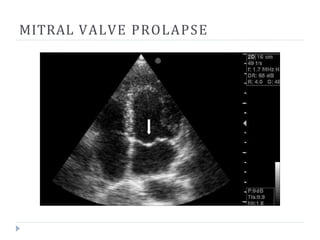

MITRAL VALVE PROLAPSE